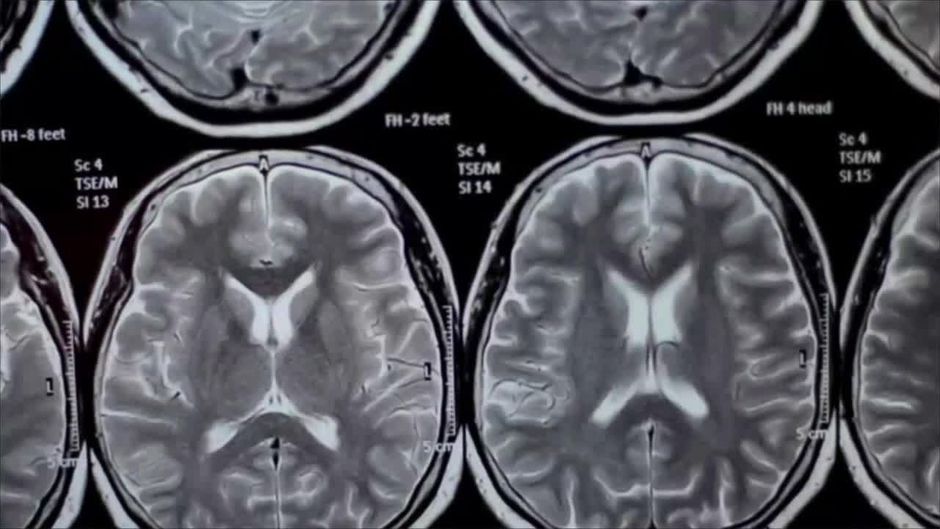

Drogen sollten nie unterschätzt. Verschiedene Forschergruppen haben nun untersucht, was im Gehirn passiert, wenn jemand Drogen konsumiert.